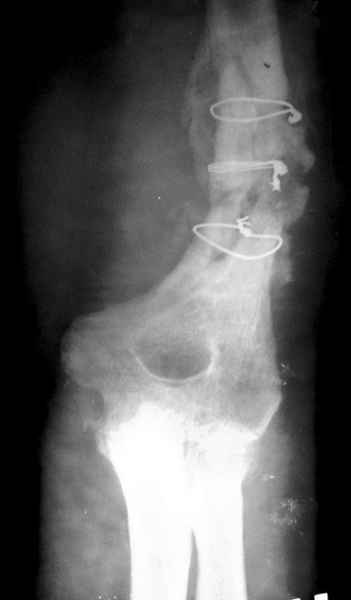

На примере два случая, извиняюсь за качество снимков, снимки и случаи из бывшего союза.

Первая больная с "успехом" была прооперирована 6 раз различными методами открытого и закрытого

остеосинтеза, включая то, что в Кисловодске заезжим австралийским "кудесником" на ложный сустав уложена скорлупа от страусиновых яиц. Последняя операция одиноким локинг плейт в одной из клиник.

Через год по поводу тех же проблем сделали ревизию, оригинальную пластину оставили как есть, только укрепили добавлением еще одной пластины и сделали костную пластику.

Через два месяца увидели признаки консолидации.

Второй случай, также после множественных операций:

пластина, аппарат, серкляж и парез нерва.

Также ревизия, из-за низкого состояния доступ был

сделан через остеотомию локтевого отростка.

Ложный сустав фиксирован двумя локинг плейт с

аутокостной пластикой, также через два месяца увидели признаки консолидации.

Движение в суставе разрешили в две недели.